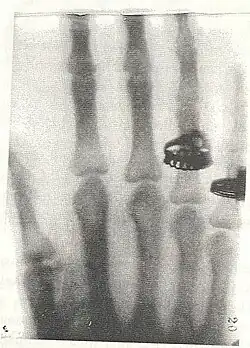

Nach dem Besuch der Schule in Merseburg absolvierte sie eine Ausbildung zur Zeichenlehrerin und legte 1888 an der Berliner Kunsthochschule das Examen ab. Es folgten Praktika und das Examen zur Handarbeitslehrerin. Ab 1890 war sie Schülerin an der Photographischen Lehranstalt des Lette-Vereins, ab 1891 war sie dort Assistentin und wurde schließlich 1913 Direktorin, als Nachfolgerin von Dankmar Schultz-Hencke. Sie blieb Direktorin bis 1932. Marie Kundt war damit die erste Frau, der eine höhere Fachschule für männliche und weibliche Schüler unterstellt war. Sie war wesentlich an der Entwicklung der Ausbildungen und der Berufsbilder der Technischen Assistentinnen in der Medizin und der Metallografie beteiligt. Marie Kundt arbeitete außerdem mit vielen Firmen und wissenschaftlichen Institutionen zusammen, unter anderem mit Hans Virchow von der Berliner Charité an Visualisierungsmöglichkeiten in den Bereichen Anatomie und Physiologie.